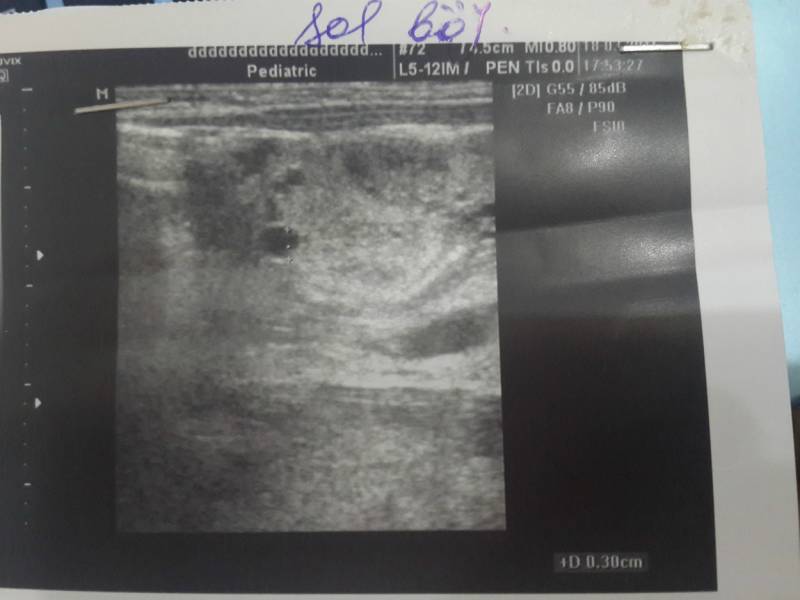

Здраствуйте еще раз!Михаил Юдович посмотрите пожалуйста наши снимки..

Судя по всему - выраженная гиперэхогенность паренхимы почек с единичными кистами без значительного увеличения размеров почек. Я бы назвал это кистозной дисплазией, и , думаю, без возможностей генетического исследования уточнить будет сложно.